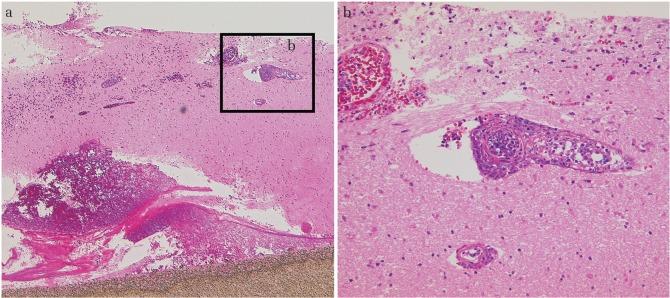

A 43-year-old man was operated on for right frontal oligoastrocytoma. 14 years after the surgery, magnetic resonance imaging and positron emission tomography revealed a new lesion near the surgical cavity. He underwent gross total resection of the lesion and implantation of bis-chloroethylnitrosourea (BCNU) wafers after intraoperative pathological diagnosis of recurrent high-grade glioma. A few days after the operation, the level of consciousness gradually worsened and left hemiparesis developed. A computed tomography scan revealed a cyst remote to the surgical cavity which did not exist 3 days prior. We performed anterior cyst wall fenestration and removed all wafers. The characteristic pathological finding at the wafer implantation site was severe inflammation within and around small vessels. This inflammatory reaction was not seen on the surface of the brain parenchyma. After surgery and rehabilitation, the patient's Karnofsky Performance Status stabilized to a pre-incident score of 90 and he returned to work. The exact pathophysiological mechanism of the cyst was not clear, but check-valve and/or osmotic gradient mechanisms related to BCNU wafer implantation could have contributed to this phenomenon. As remote cyst development happened a week after surgery, surgeons should be aware of such a rare condition when implanting wafers as consciousness impairment and hemiparesis may occur. Close radiological follow-up is therefore necessary.

一名43岁男性因右侧额叶少突星形细胞瘤接受手术。术后14年,磁共振成像和正电子发射断层扫描显示手术腔附近出现新病灶。术中病理诊断为复发性高级别胶质瘤后,他接受了病灶的大体全切并植入了双氯乙基亚硝脲(BCNU)晶片。术后几天,意识水平逐渐恶化并出现左侧偏瘫。计算机断层扫描显示手术腔远处有一个囊肿,而3天前并不存在。我们进行了前囊肿壁开窗术并取出了所有晶片。晶片植入部位的特征性病理发现是小血管内部及周围有严重炎症。脑实质表面未见这种炎症反应。经过手术和康复治疗,患者的卡氏功能状态评分稳定在发病前的90分,他恢复了工作。囊肿的确切病理生理机制尚不清楚,但与BCNU晶片植入相关的单向阀和/或渗透梯度机制可能导致了这种现象。由于术后一周出现了远处囊肿,外科医生在植入晶片时应意识到这种罕见情况,因为可能会出现意识障碍和偏瘫。因此,密切的影像学随访是必要的。